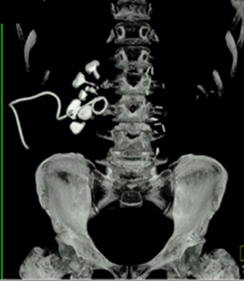

Vad ses på bilden?

Samlingssystemet med uttalad hydronefros, uttalad hydrouretär ned till konkrement i övergång mellan proximal uretär och mellersta delen ureätär

DT visar

• Samlingssystemet med uttalad hydronefros, uttalad hydrouretär ned till konkrement i övergång mellan proximal uretär och mellersta delen ureätär